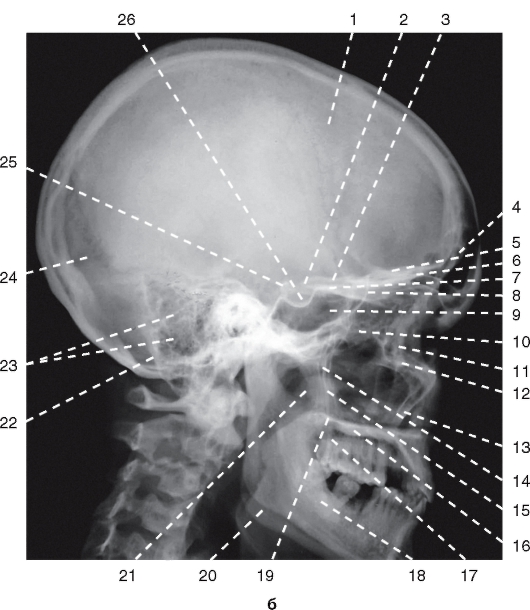

КТ анатомия сосцевидного отростка: особенности и показания

Раздел: Галерея прозрений